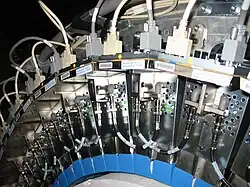

Der Detektor eines heute erhältlichen PET-Scanners besteht aus mehreren Detektorringen, die jeweils aus 30–40 Detektormodulen aufgebaut sind. Ein Detektormodul besteht aus 4–8 Detektorblöcken. Ein Detektorblock besteht aus mehreren Einzelkristallen (z. B. in der Anordnung 4×4, 4×5 oder 6×6). Die Abmessungen der Kristalle bewegen sich im Bereich von 6 bis 8 mm in transaxialer Richtung. In radialer Richtung – also in Einfallsrichtung der Photonen – beträgt die Kristalldicke meist zwischen 20 und 30 mm. In der Summe ergibt dies ca. 10.000 ringförmig angeordnete Detektorkristalle (Szintillationszähler), die bei analogen Systemen mit ca. 1000 Photomultipliern gekoppelt sind. Das Konstruktionsprinzip, bei dem ein Block von Photomultipliern auf ein Array von Szintillationskristallen „blickt“, wurde im Jahr 1986 eingeführt und hat sich seither bewährt.[4]

Szintillationsnachweis

In den klinischen PET-Systemen bis in die 2020er Jahre wurden für den Nachweis der Szintillationen Photomultiplier verwendet, da es damals die empfindlichsten Nachweisinstrumente für die sehr schwachen Lichtblitze waren. Heute, Mitte der 2020er Jahre, gibt es sowohl niederpreisige analoge Systeme, wie auch höherpreisige digitale Systeme. Ein Beispiel für ein im Jahr 2024 mit analogen Photomultipliern arbeitendes Gerät ist bei GE der Discovery IQ, digital akquiriert der Omni Legend. Bei Siemens ist der Biograph Horizon mit Photomultipliern ausgestattet, der Biograph Trinion arbeitet digital. United Imaging hat nur noch digitale Systeme. Das Vereos System von Philips arbeitet digital.[7]

Photomultiplier

Die Szintillationskristalle werden entweder eingesägt, oder mehrere Kristalle werden miteinander verklebt. An den Kristallgrenzen kommt es zur Reflexion der Photonen, die so in Richtung der Detektoren gelenkt werden. Dies ermöglicht eine genauere Lokalisation als in einem homogenen, einzelnen Kristallblock. Mehrere Photomultiplier „blickten“ zusammen auf eine Gruppe von Szintillationskristallen und waren entweder direkt oder über Lichtleiter mit dem Szintillationskristall verbunden. Die Lokalisation der Szintillationen erfolgt nach dem Prinzip der Anger-Kamera durch Wichtung der Helligkeit der in den Photomultipliern registrierten Szintillationen.

Halbleiterdetektoren